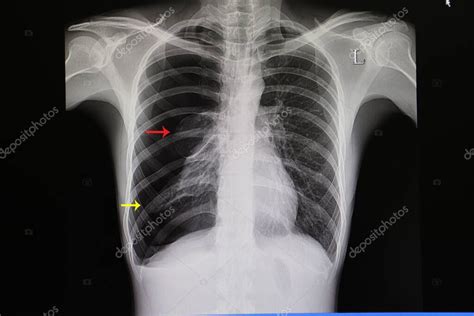

El diagnóstico de neumotórax se basa en la clínica, la exploración física y pruebas de imagen.

- Radiografía de Tórax: Es la herramienta diagnóstica inicial estándar. Se realiza una radiografía postero-anterior y en inspiración. En ocasiones, una radiografía en espiración forzada puede favorecer la visualización de neumotórax de pequeño tamaño.

- Tomografía Axial Computarizada (TAC) de Tórax: Se recurre a ella en casos específicos para identificar posibles bullas, blebs o lesiones pulmonares subyacentes, especialmente cuando el diagnóstico no está claro con la radiografía simple o para descartar patología que sugiera un neumotórax espontáneo secundario. No se recomienda de forma sistemática tras un primer episodio de NEP.

El tamaño del neumotórax se define como el porcentaje del hemitórax que está vacío, calculado mediante fórmulas específicas. Los neumotórax pequeños (<10%) pueden pasar desapercibidos en la radiografía de tórax y requieren un rastreo cuidadoso de los reparos pulmonares.